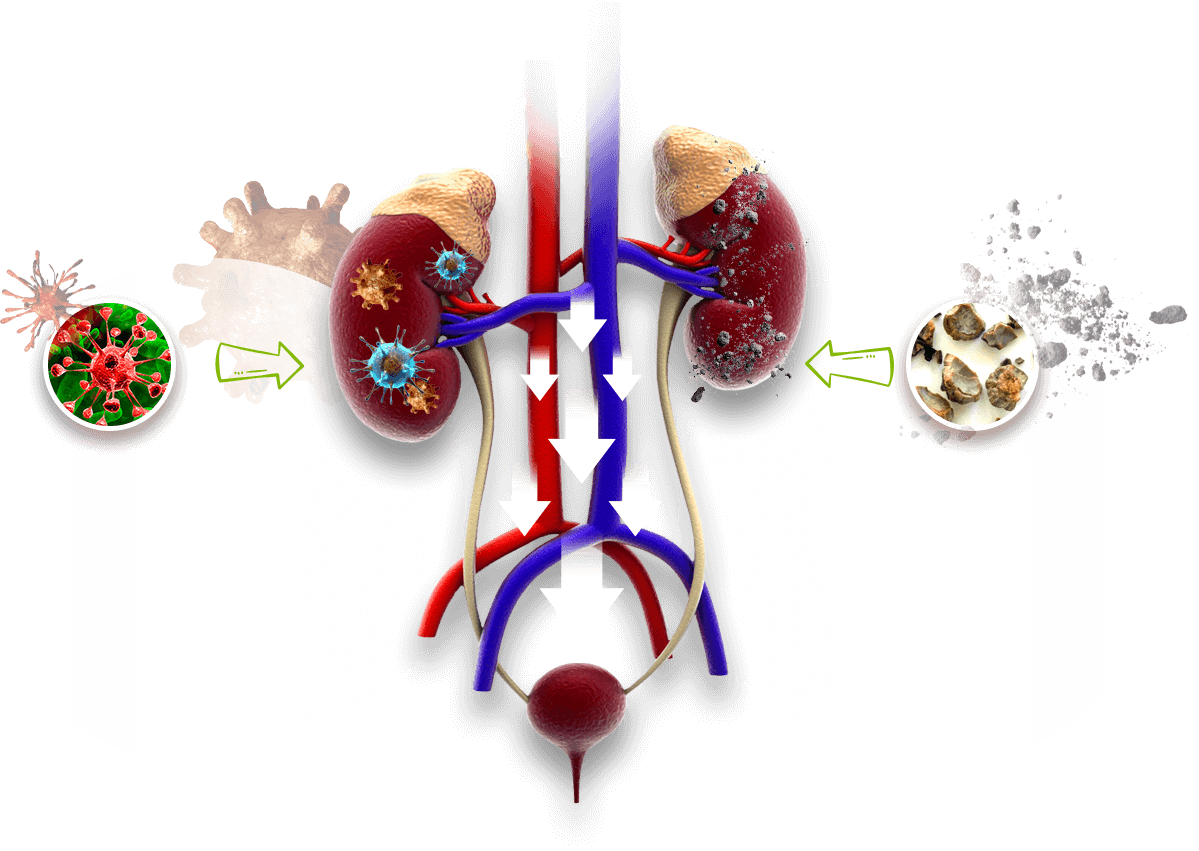

Bubrežne kolike

predstavljaju najsnažniji bol koji čovek može izdržati

Drhtavica

Lupanje srca

Oštar bol

Bolni šok u 6% slučajeva

Mučnina i povraćanje

Bubrežne kolike se uvek javljaju iznenada. U 75% slučajeva kod naizgled zdravih ljudi. U 87% slučajeva, bubrežne kolike predstavljaju pogoršanje stanja s kamenjem u bubrezima. U ranim stadijumima stvaranja kamenja u bubregu nema nikakvih simptoma. Čovek je aktivan, čio i ne sumnja da je u njegovom telu već pokrenut proces uništavanja.

Delovanje

Ove biljke su prirodni diuretici. Kada dođu u organizam, karlice bubrega se nadražuju i pojačavaju odvođenje mokraće. Zajedno s mokraćom iz organizma odlazi i višak soli, minerala i štetnih materija koje izazivaju pojavu kamena u bubregu i komplikacije povezane s njim.

Ako je kod vas kamen u bubregu tek počeo da se stvar (a vi za to ne znate jer vas ništa ne boli), Nefro Aktiv će isprati pesak i sitno kamenje iz bubrega, sprečiti stagnaciju i neće dozvoliti razvoj bolesti.